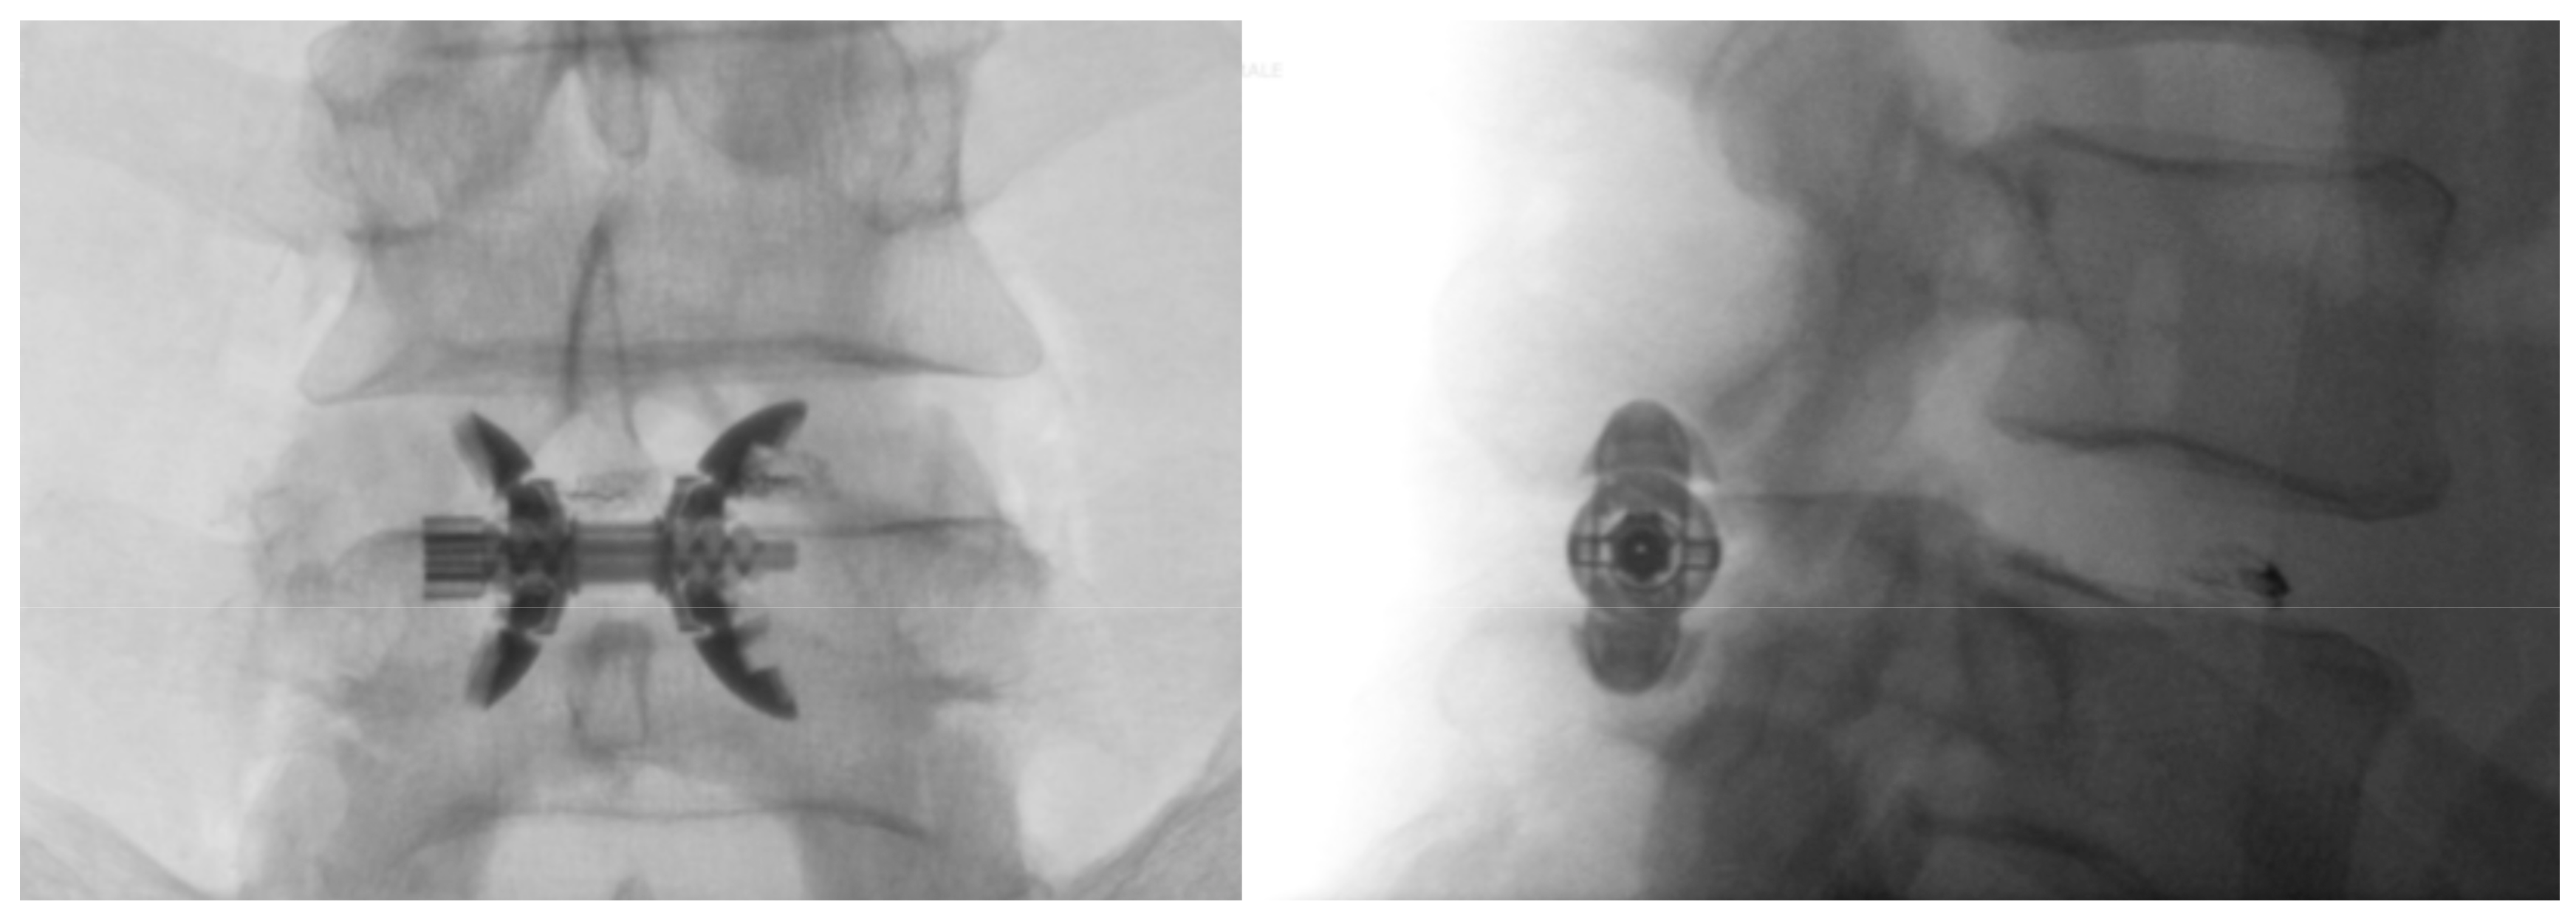

Superion interspinous spacer in situ. (a) A/P view, (b) lateral view Types Of Interspinous Spacers    summary of background data: Once it is inserted between two vertebrae, the spacer’s arms open around the spinous process of the lumbar spine to lock the device into place. Lumbar interspinous spacers (isps) have recently become popular as an alternative.   minimally invasive interspinous process devices (ipd), including interspinous.  interspinous spacers offer an effective treatment option for patients. Types Of Interspinous Spacers.